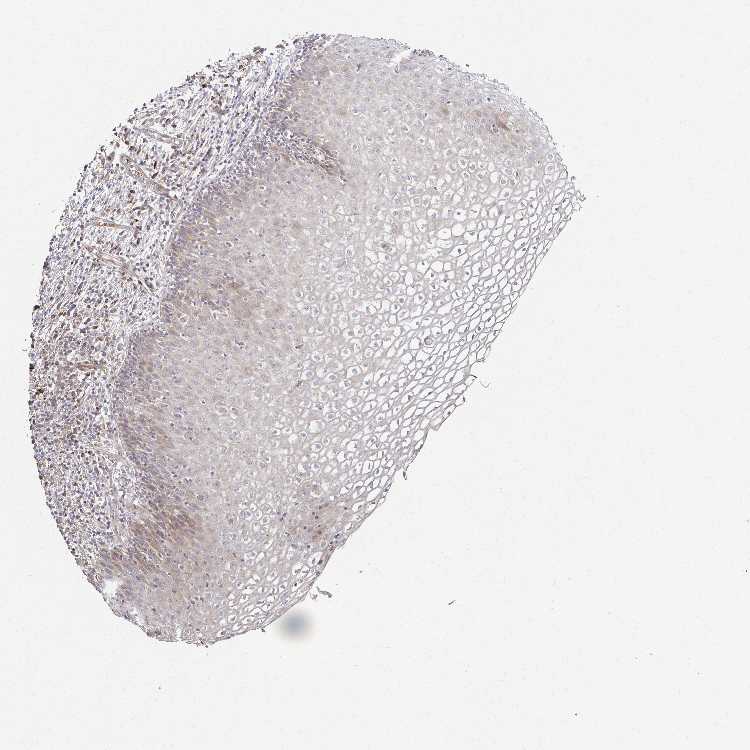

CERVIX - Antibody stainingi

Antibody staining in the annotated cell types in the current human tissue is reported as not detected, low, medium, or high, based on conventional immunohistochemistry profiling in selected tissues. This score is based on the combination of the staining intensity and fraction of stained cells.

Each image is clickable and will lead to virtual microscopy that enables deeper exploration of all samples and also displays staining intensity scores, fraction scores and subcellular localization as well as patient and tissue information for each sample.

Antibody HPA059235

Glandular cells Not detected

Squamous epithelial cells Low